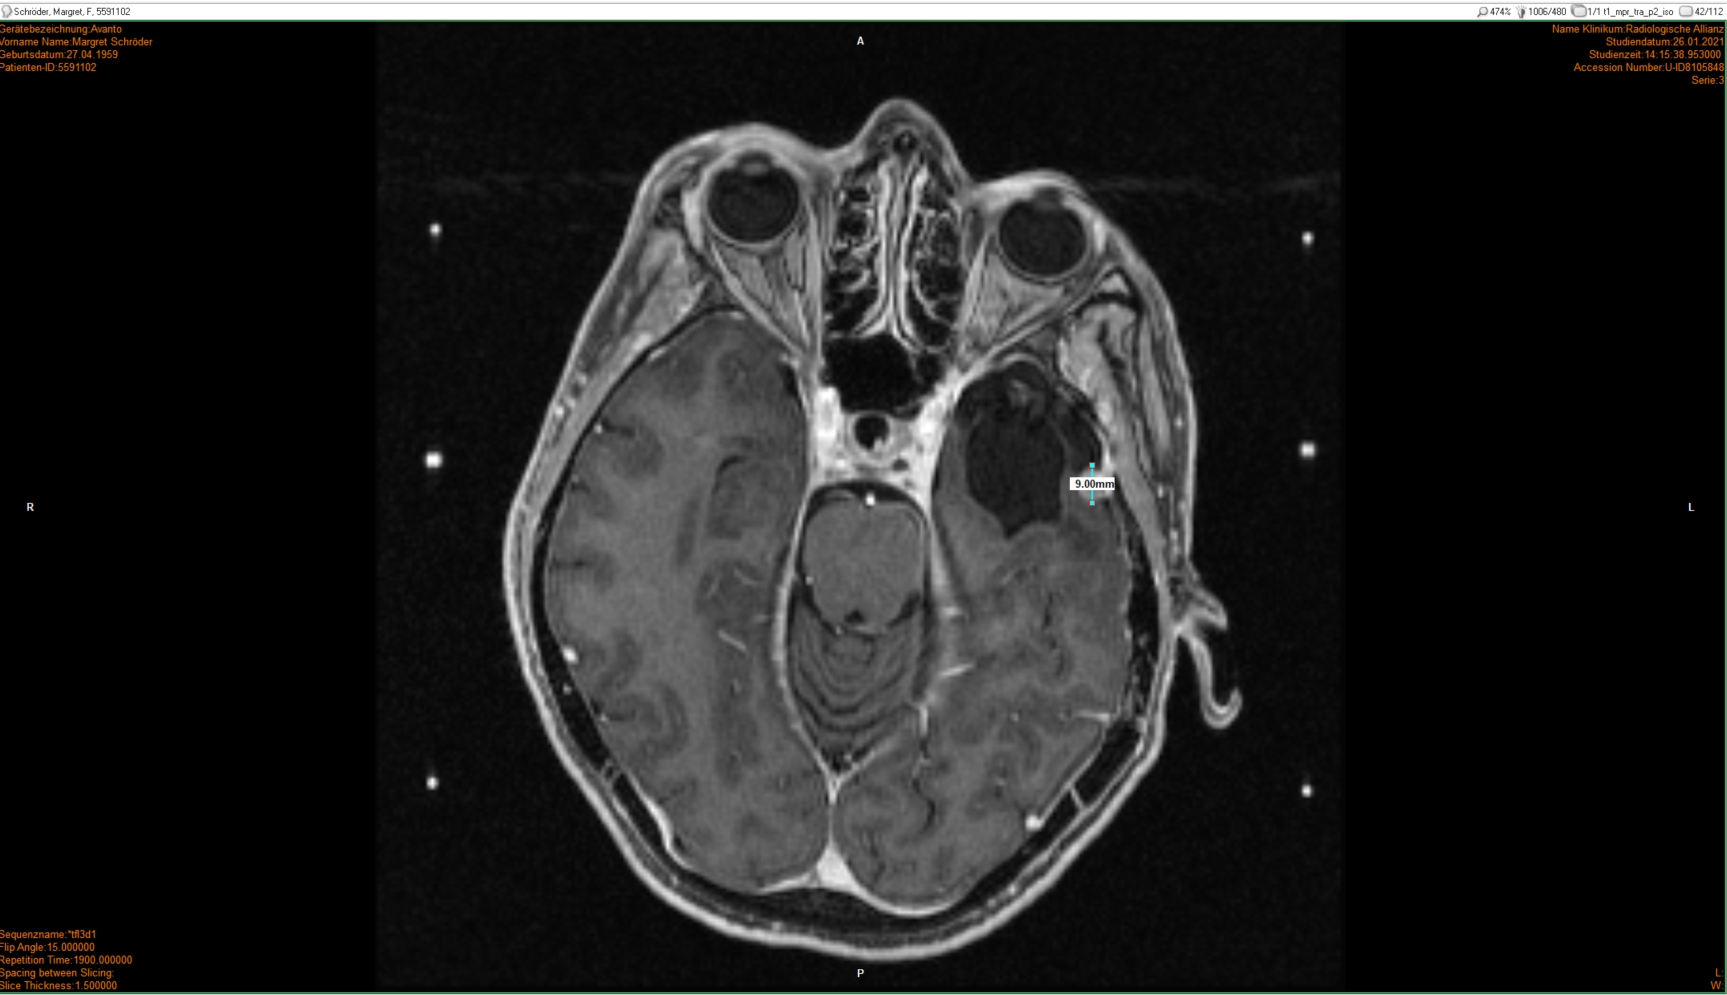

26.01.2021: Gamma-Knife

• GammaKnife-Behandlung eines kleinen links temporal duraständig gelegene Konvexitätsmeningeom (postoperatives Rezidiv)

13 x 9 x 10 mm,Volumen 0,53 cm3 , Minimumdosis 20 Gy.